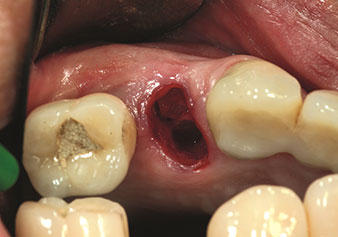

One application, which is often underestimated is the atraumatic extraction of tooth roots or root fragments in the scope of alveolar management. The fine periotomes, which are currently available in two versions (EX1 and EX2 from W&H), can also be used to remove teeth which have previously undergone special endodontic treatment or ankylosed roots with ease. This results in extraction alveoli where both the hard and soft tissue are fully intact as it is generally possible to avoid reflection.

This establishes the optimal basis for subsequent or immediate implant treatment (Figures 1 and 2 included with the kind permission of Dr Torsten Conrad, Bingen a. Rhein).